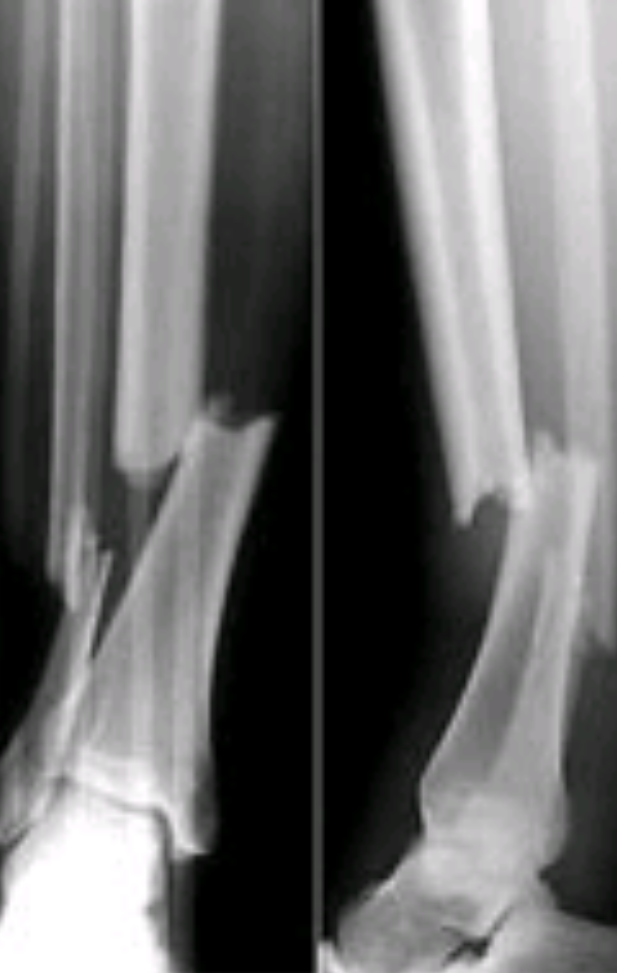

Denk an einen feinen Riss in einer Porzellantasse. Das ist anders als wenn die ganze Tasse in tausend Stücke zerspringt, richtig? Genauso ist es beim Becken. Ein kleiner, stabiler Bruch, wo die Knochen nicht großartig verschoben sind, heilt schneller als ein komplizierter Bruch, der vielleicht sogar operiert werden muss.

Stabile Brüche, die man oft "Haarrisse" nennt, können tatsächlich innerhalb von 8 bis 12 Wochen verheilen. Du musst dir das so vorstellen: Der Körper ist ein Meisterhandwerker. Er fängt sofort an, den Bruch zu reparieren, indem er neues Knochengewebe bildet. Und je weniger kaputt ist, desto schneller geht's.

Komplizierte Brüche hingegen… tja, da kann es schon mal 3 bis 6 Monate dauern, oder sogar länger. Und das ist noch nicht alles. Denn: